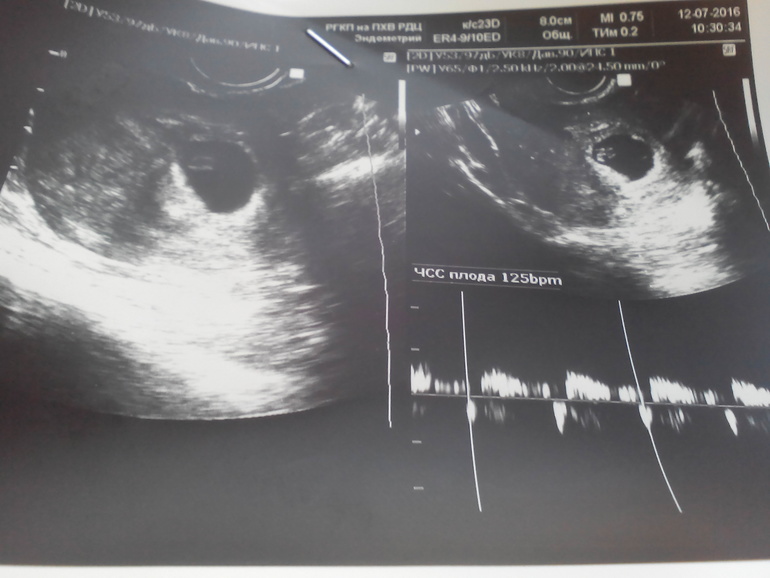

УЗИ, КТГ, доплерПривет девчулечки!!!!! Вчера была на УЗИ, сердечко бьётся, счастлива!!!! только поставили небольшую угрозу, немного переживаю. Нужно поберечься, а так все хорошо, не передать ощущения) слышала сердечко малыша.... Теперь я официально беременна)))